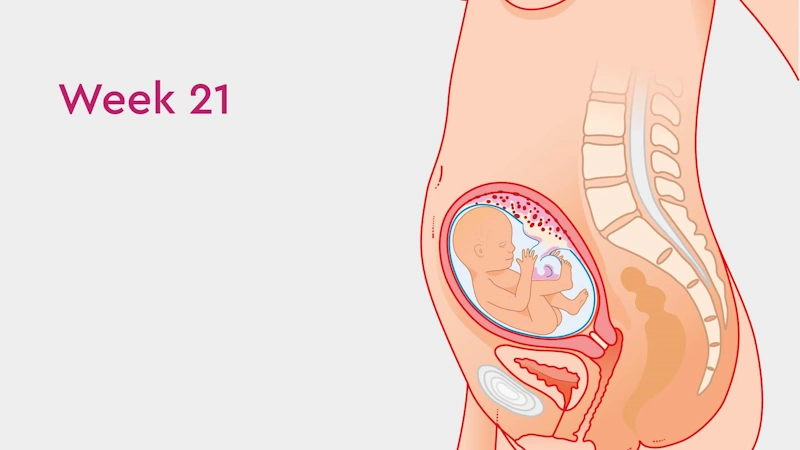

Ҳафтаи 21-уми ҳомиладорӣ яке аз марҳилаҳои ҷолиб ва пурэнергияи давраи модаршавӣ ба ҳисоб меравад. Дар ин вақт ҷанини шумо тақрибан 18–25 сантиметр қад ва тақрибан 390–400 грамм вазн дорад — ба андозаи як банани калон. Ӯ дар дохили моеъи амниотикӣ озодона ҳаракат мекунад, дасту по меандозад ва фазои кофӣ дорад, то ки чарх занад, тебпалезад ва бо қувваи бештар ҷунбад.

Ин ҳафта давраи муҳим барои рушди системаи асаб мебошад: мағзи ҷанин бо суръати баланд инкишоф меёбад, пайвастҳои нави асабӣ пайдо мешаванд ва ҳамоҳангии мушакҳои ӯ беҳтар мегардад. Аз ҳамин сабаб теппазаниҳо ва ҳаракатҳои ҷанин равшантар ва мунтазамтар эҳсос мешаванд. Бисёр модарон дар ин марҳила аввалин бор имконият меёбанд, ки ҷунбиши ҳақиқии ҷанинро эҳсос кунанд ва ҳатто падар метавонад ҳаракатро аз берун ҳис кунад.

Ин марҳила оғози нисфи дуюми ҳомиладорӣ аст — даврае ки ҳам шумо ва ҳам ҷанин ба рушди устувор ва калоншавии босуръат ворид мешавед.

Дар ин ҳафта ҷанин ба нисфи вазни таваллуд мерасад. Ӯ давра ба давра бедор ва хоб мешавад ва ин сабаб мешавад, ки шумо дар як соат чанд маротиба теппазанӣ ҳис кунед.